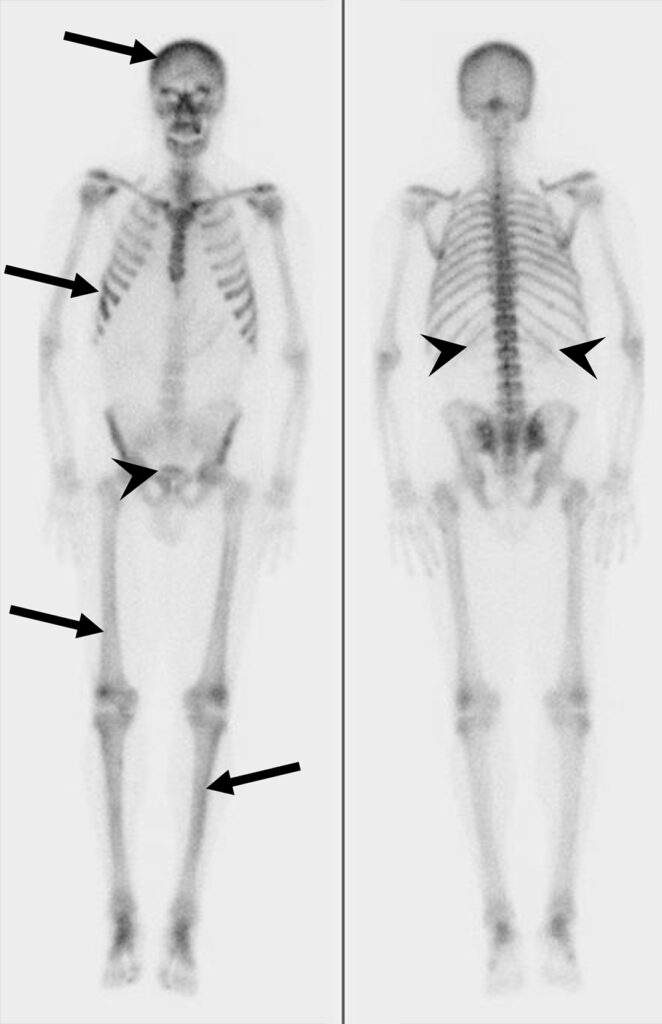

Scintigrafia ossea di un paziente con metastasi ossee da tumore prostatico.

Superscan in un uomo di 68 anni con cancro alla prostata.

(A) Le scintigrafie ossee whole-body in proiezione anteriore e posteriore con 99mTc-MDP mostrano una captazione diffusa nello scheletro assile e appendicolare prossimale, con una captazione nei tessuti molli e renale significativamente ridotta rispetto all’assorbimento scheletrico, compatibile con un aspetto in “superscan” secondario a diffuse metastasi osteoblastiche. (B) L’immagine TC dell’addome con ricostruzione coronale mostra diffuse metastasi ossee sclerotiche che coinvolgono il rachide lombare, il bacino e i femori prossimali. La malattia metastatica può manifestarsi in modo variabile, spaziando da lesioni blastiche a litiche e da lesioni solitarie a multifocali.